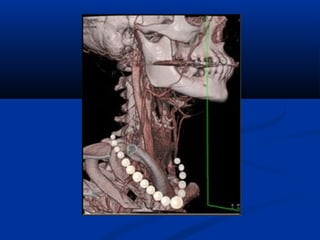

U maùu vuøng haømU maùu vuøng haøm

(T)/(T)/ Daõn tónh maïchDaõn tónh maïch

caûnh ngoaøi (T)caûnh ngoaøi (T)

Taùi taïo 3DTaùi taïo 3D

U maùu vuønghaømU maùu vuøng haøm (T)/(T)/ Daõn tónh maïchDaõn tónh maïch caûnh ngoaøi (T)caûnh ngoaøi (T)